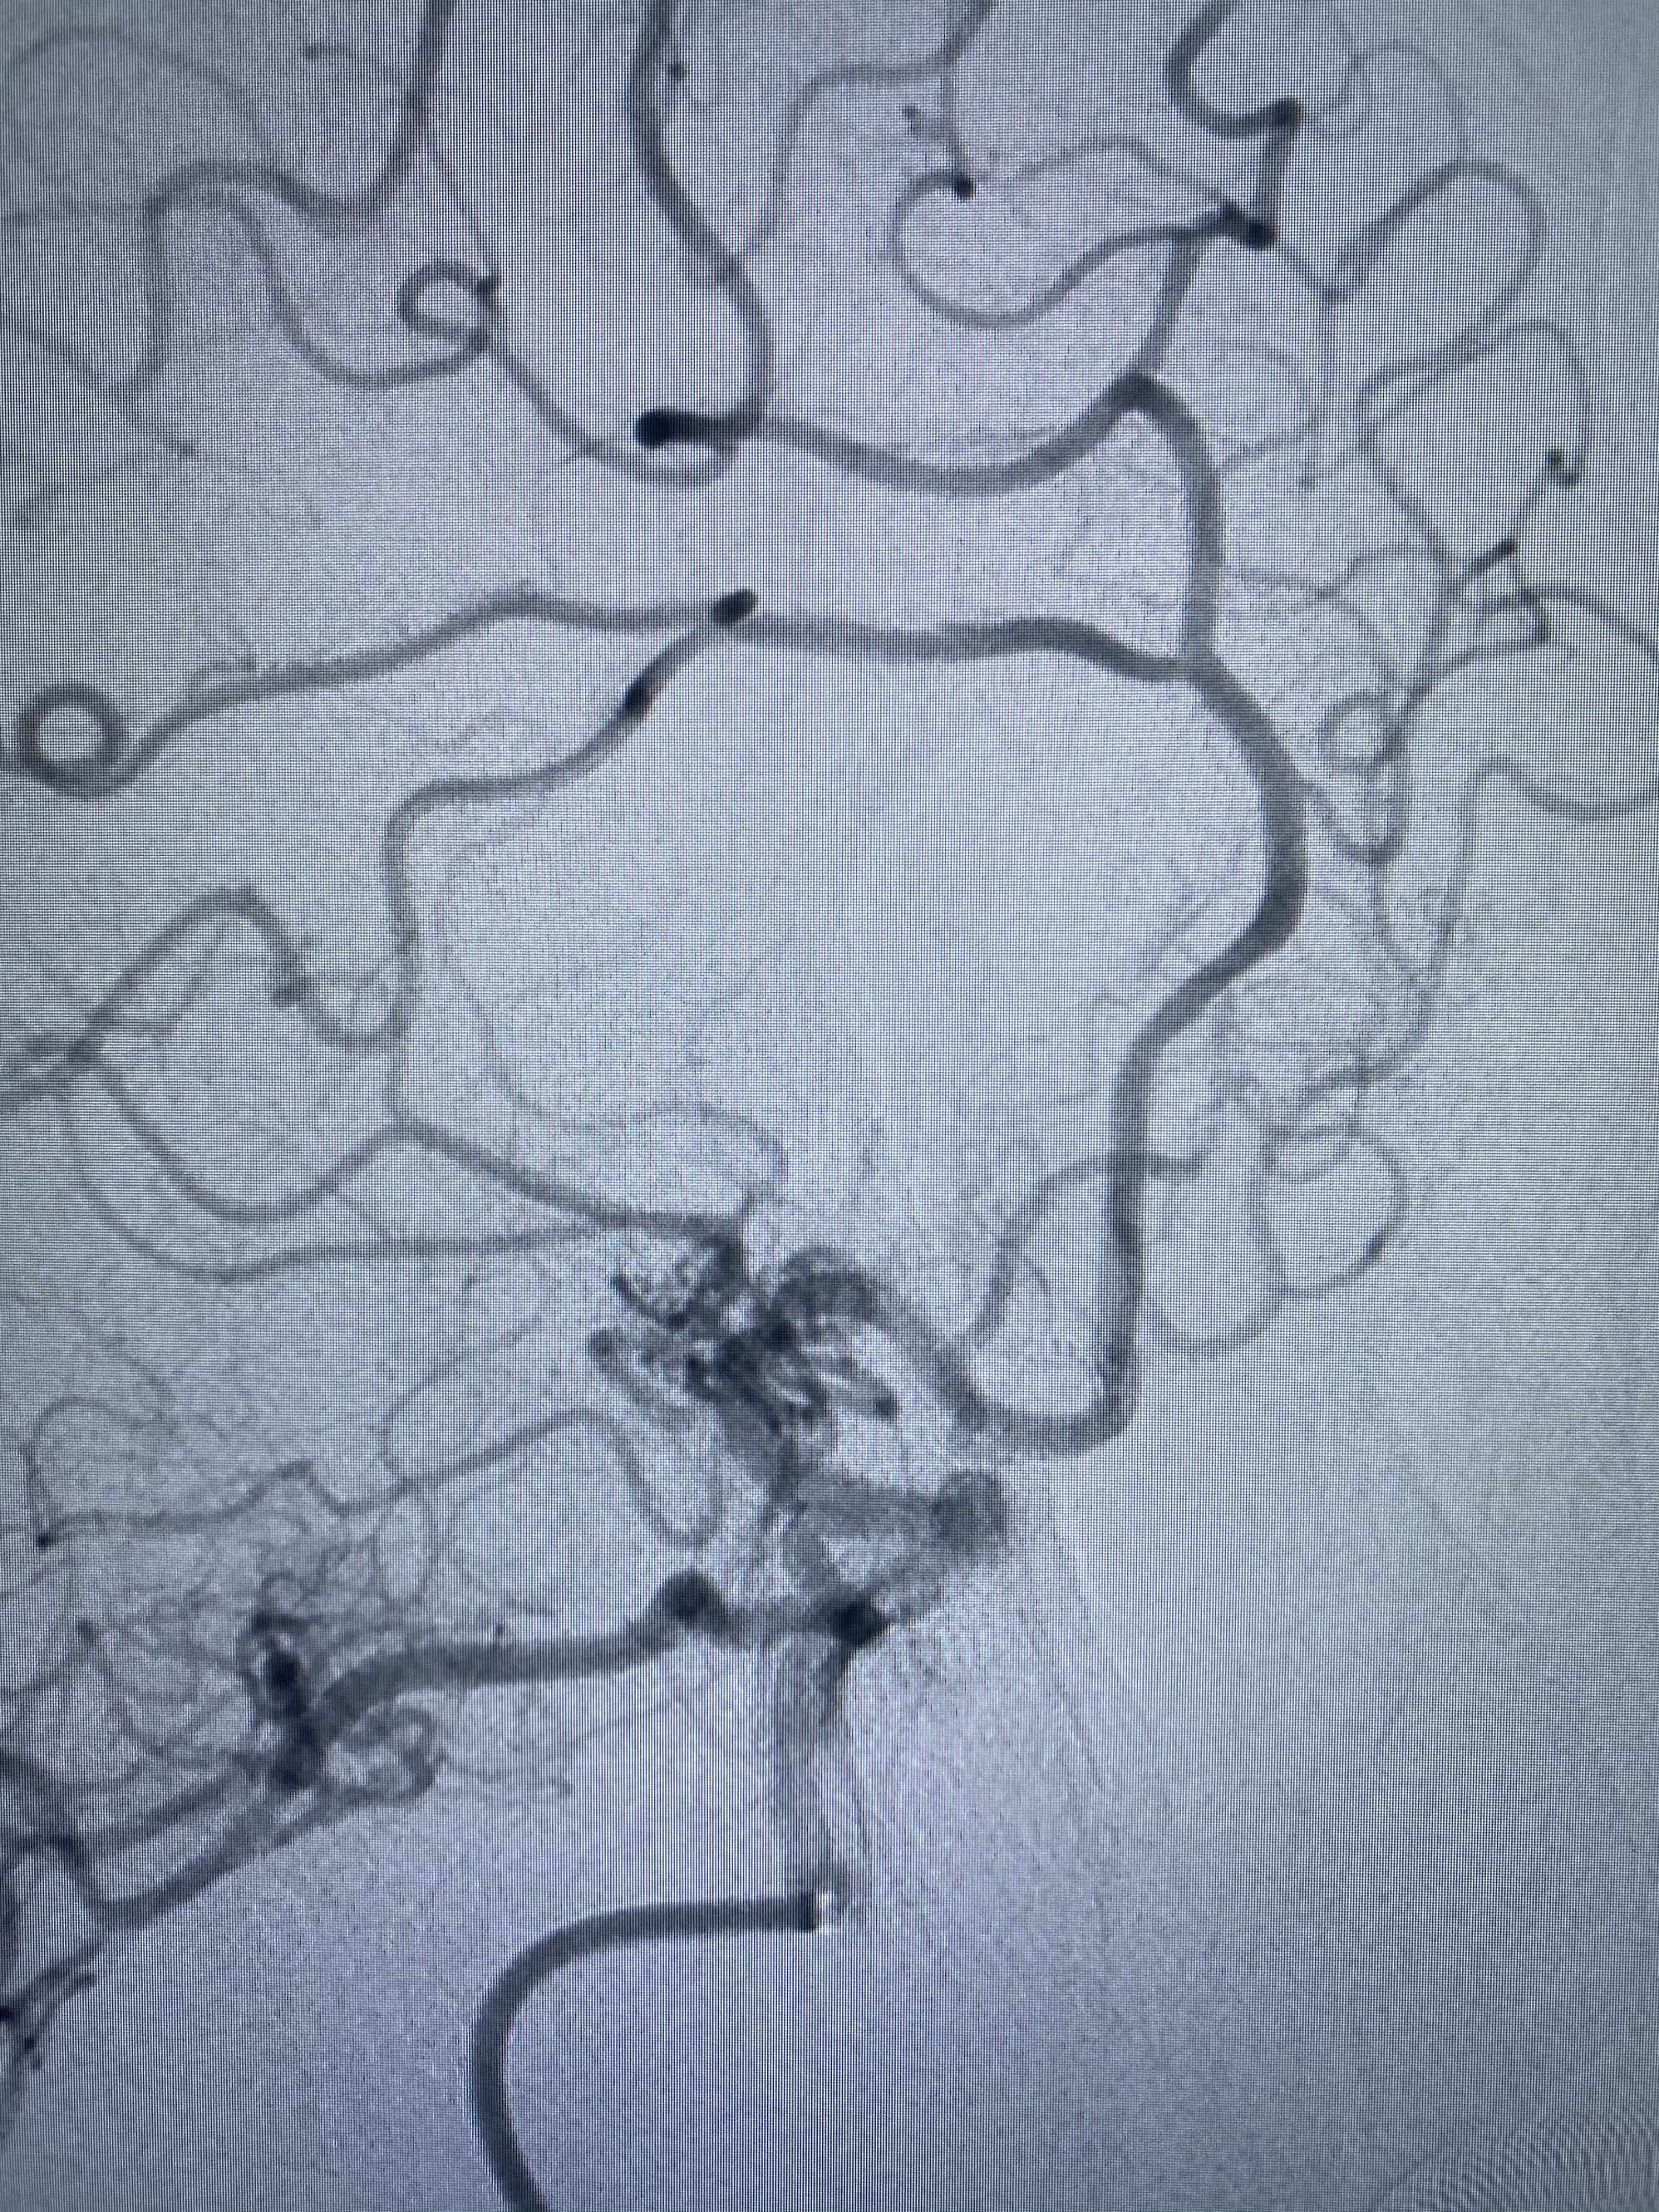

MLS,M79Y,sah,双侧MCA烟雾病,Heubner返动脉瘤,前交通段开窗,细支发出Heubner返动脉,瘤颈细长,瘤颈口比微导管细,弹簧圈2mmx3cm“隔山打牛”填塞治愈,Heubner返动脉保留。

Heubner返动脉是由大脑前动脉A1末端发出的豆纹动脉,由于走形和A1段相反,故称Heubner返动脉,该动脉梗塞可能引起尾状核头梗塞,引起偏瘫和面瘫,便身震颤等症状。